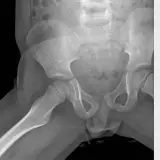

Over 2,100 interactive radiology cases, curated by radiologists for your level of training. Scroll, window, and view cases full screen โ€” just like on PACS. Click linked findings in each writeup to jump straight to them on the image. Cases include sample reports, a focused discussion section, original illustrations, and videos.

Casi completamente interattivi con gli strumenti che ti aspetti su un PACS: scroll, windowing, zoom, pan, misurazioni, ROI e modalitร  a schermo intero.

Annotazioni dettagliate evidenziano i reperti chiave direttamente sui casi. Clicca sui reperti collegati nella descrizione del caso per saltare alla loro esatta posizione sullo scan.